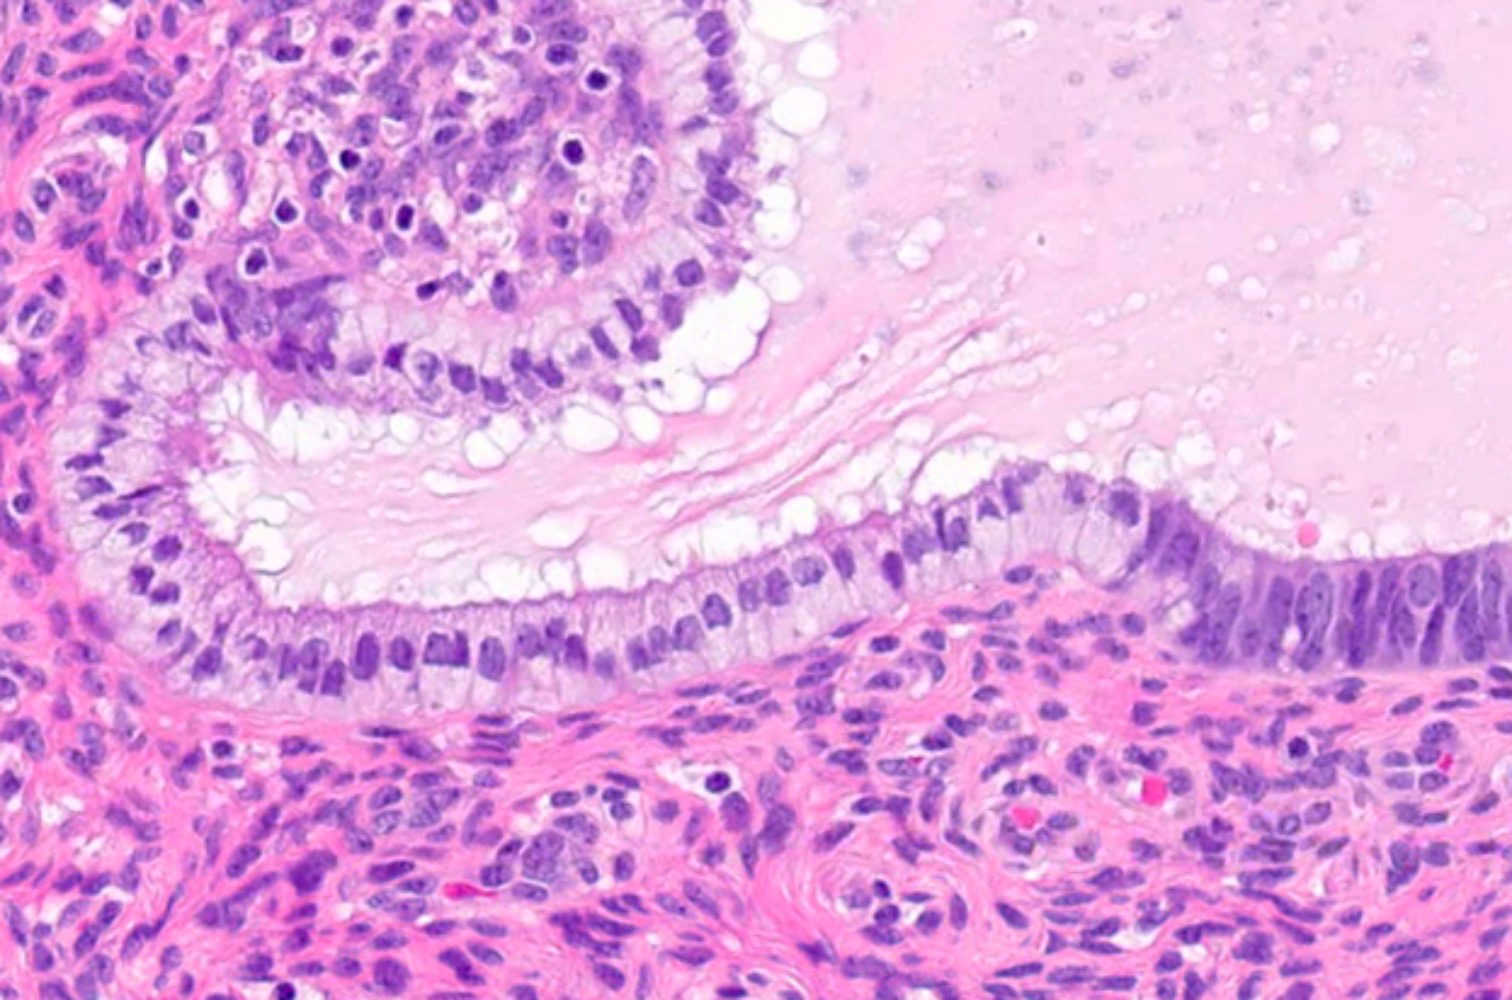

Microscopic (histologic) images

Contributed by Jessica L. Bentz, M.D.

- Tubal metaplasia (Mod Pathol 2011;24:1254):

- Resembling fallopian tube epithelium; pseudostratified with ciliated eosinophilic cells and clear round cells

- Mucinous metaplasia (Gynecol Oncol 2015;136:389, Diagn Pathol 2017;12:39):

- Cuboidal to columnar cells, most commonly resembling endocervical epithelium

- Rarely, resembling gastric and intestinal type metaplasia

- Generally cytologically bland

- Subtypes (Mod Pathol 1999;12:1137):

- Type A: single cell layer lining the epithelial surface, with or without glandular involvement

- Type B: focal / patchy papillary / micropapillary changes

- Type C: extensive papillary, cribriform or microacinar architecture